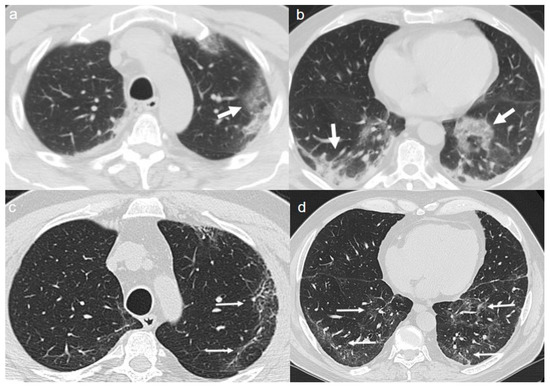

On admission, chest CT showed patchy areas of GGO with in upper lobes (Figure 4a,b), in the middle and left lower lobe (Figure 5a,b).

A CT at 4 months from the onset of symptoms showed the bilateral persistence of fibrotic stripes (Figure 4c,d and Figure 5c,d).

Figure 4. (a,b) CT shows patchy areas of GGO with in the upper lobes (arrows). (c,d) CT after 4 months from the onset of symptoms shows bilateral persistence of fibrotic stripes in upper lobes (thin arrows).

Figure 5. (a,b) CT shows patchy areas of GGO in the middle lobe (arrow in a) and in the left lower lobe (arrow in b). (c,d) CT after 4 months from the onset of symptoms shows bilateral persistence of fibrotic stripes in middle lobe (thin arrow in c) and in left lower lobe (thin arrows in d).